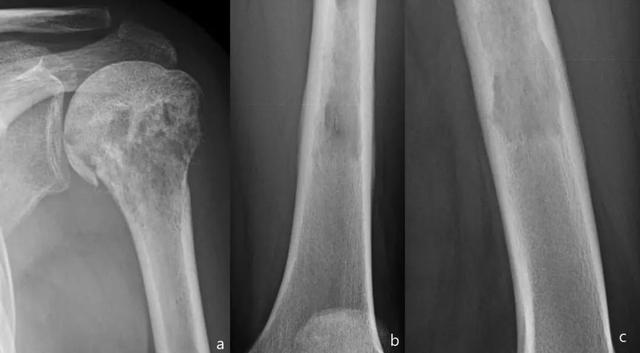

多发性疾病(65%)比单一性疾病更普遍。最常见的受累部位是骨盆,脊柱,头骨和近端长骨。

在头骨中,更常见的发现是剪纸画样的骨质疏松(大,明确的裂解病变),板障扩大和姚蜜昂样形态(混合溶解和硬化病变)。

脊柱:相框标志(包裹椎体边缘的皮质增厚和硬化),椎骨的平方和垂直小梁增厚比骨内血管瘤中看到的模式更粗糙。

长骨:草叶或蜡烛火焰标志:开始作为透明度的软骨下区域,具有V形骨溶解的前端,向骨干延伸。

骨闪烁显示疾病的所有阶段的摄取显着增加(图20)。

图20:患者病程10年。颅骨的侧位X线片(a):颅骨中大的明确的溶解病变,内颅骨表和外颅骨表都涉及(局限性骨质疏松)。胫骨的侧位X线照片(b):具有V形前端的透明度的软骨下区域骨溶解,向骨干延伸。除图像外,血清碱性磷酸酶(ALP)和尿羟脯氨酸升高证实了Paget病在裂解阶段。